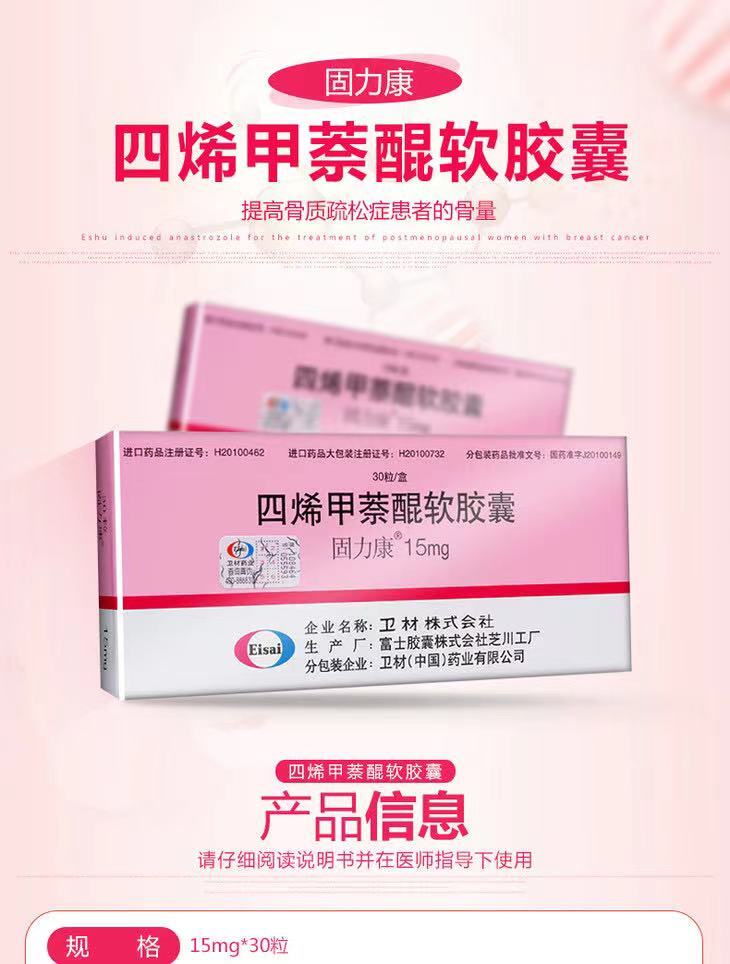

除了食物以外,现在也有专门的维生素K2制剂。一般的药品超市都有维生素K2出售,大致分为两种,一种是从纳豆里提炼出来的天然维生素K2,规格一般使用微克(ug)计量。另一种是化学合成的四烯甲萘醌,规格一般使用毫克(mg)计量。购买的时候注意分辨。

合成的维生素K2